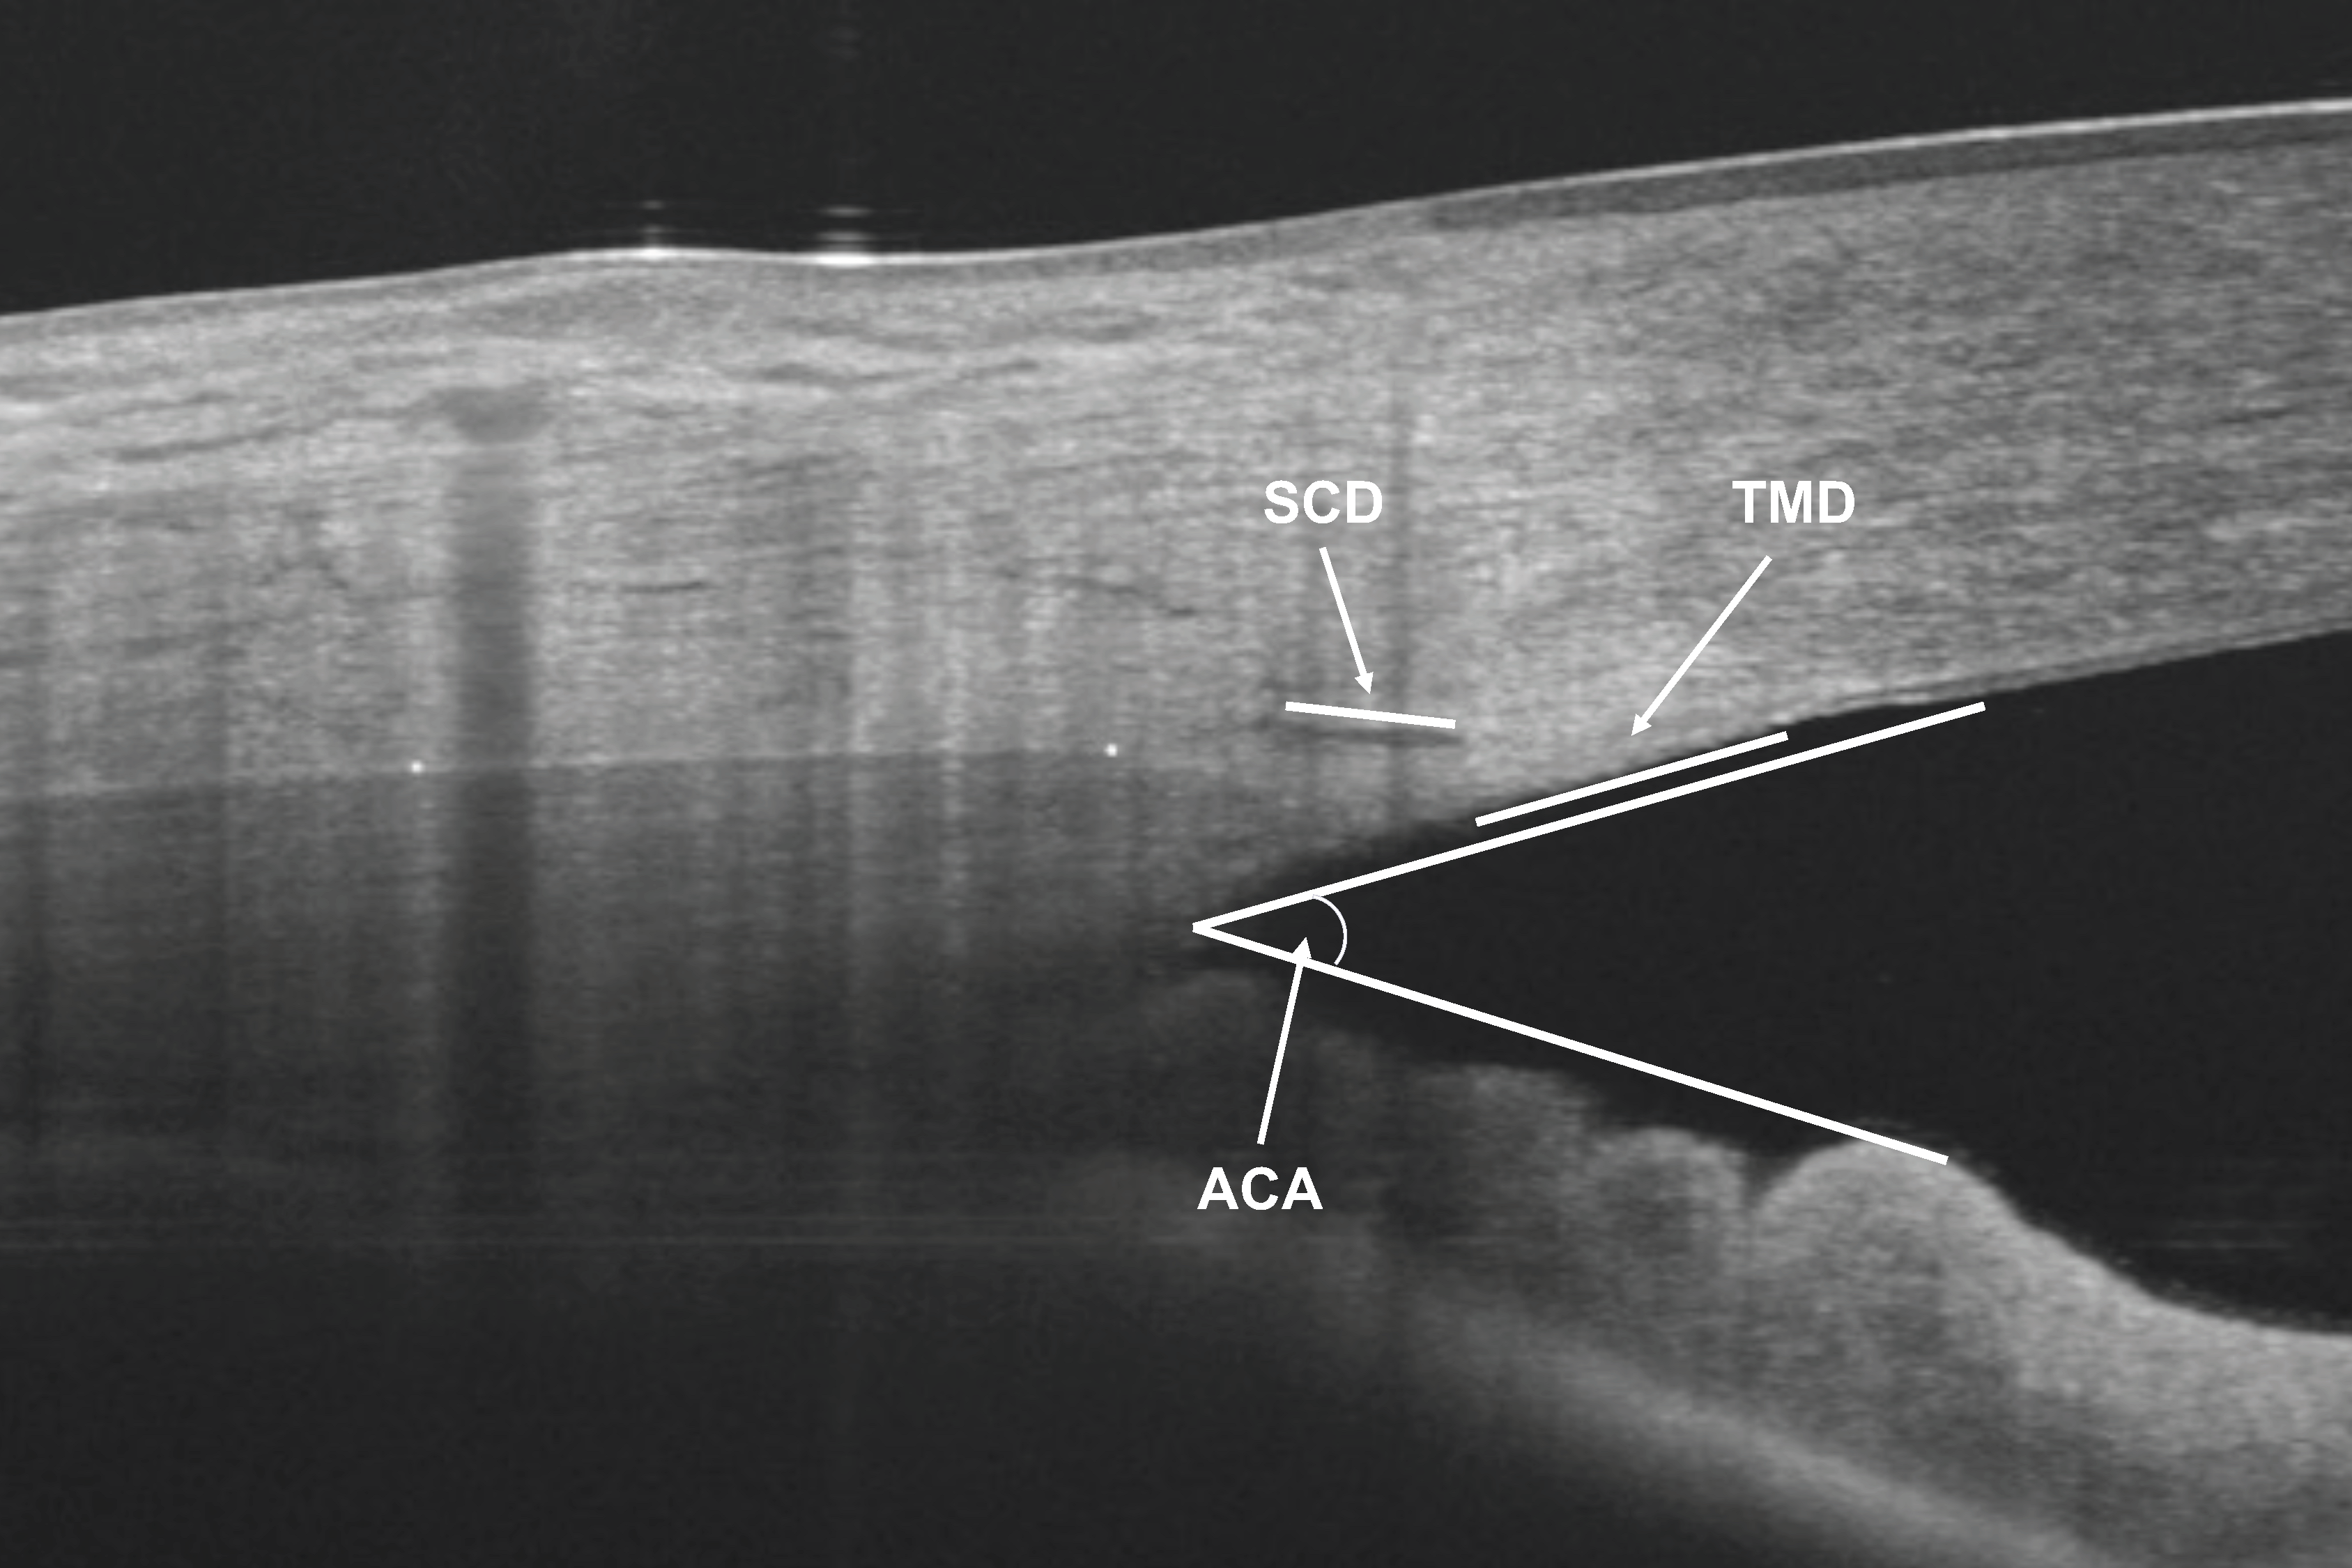

1. Introduction

2.2. Ophthalmological Examination and OCT

2.3. OCT Measurements